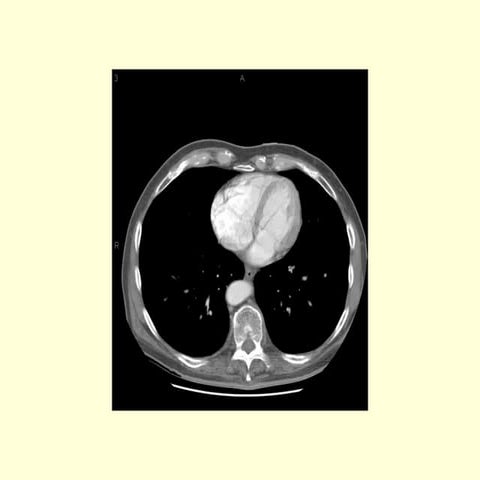

Identify the following structures in the body CT to the right. To view the location of the structure in the image click on

the label at the left and the structure will be indicated in the image. Abdominal CT scans typically begin just above

the diaphragm, so the first slice you see is of the lower chest.

Identify the followingstructures in the body CT to the right. To view the location of the structure in the image click on the label at the left and the structure will be indicated in the image. Abdominal CT scans typically begin just above the diaphragm, so the first slice you see is of the lower chest.